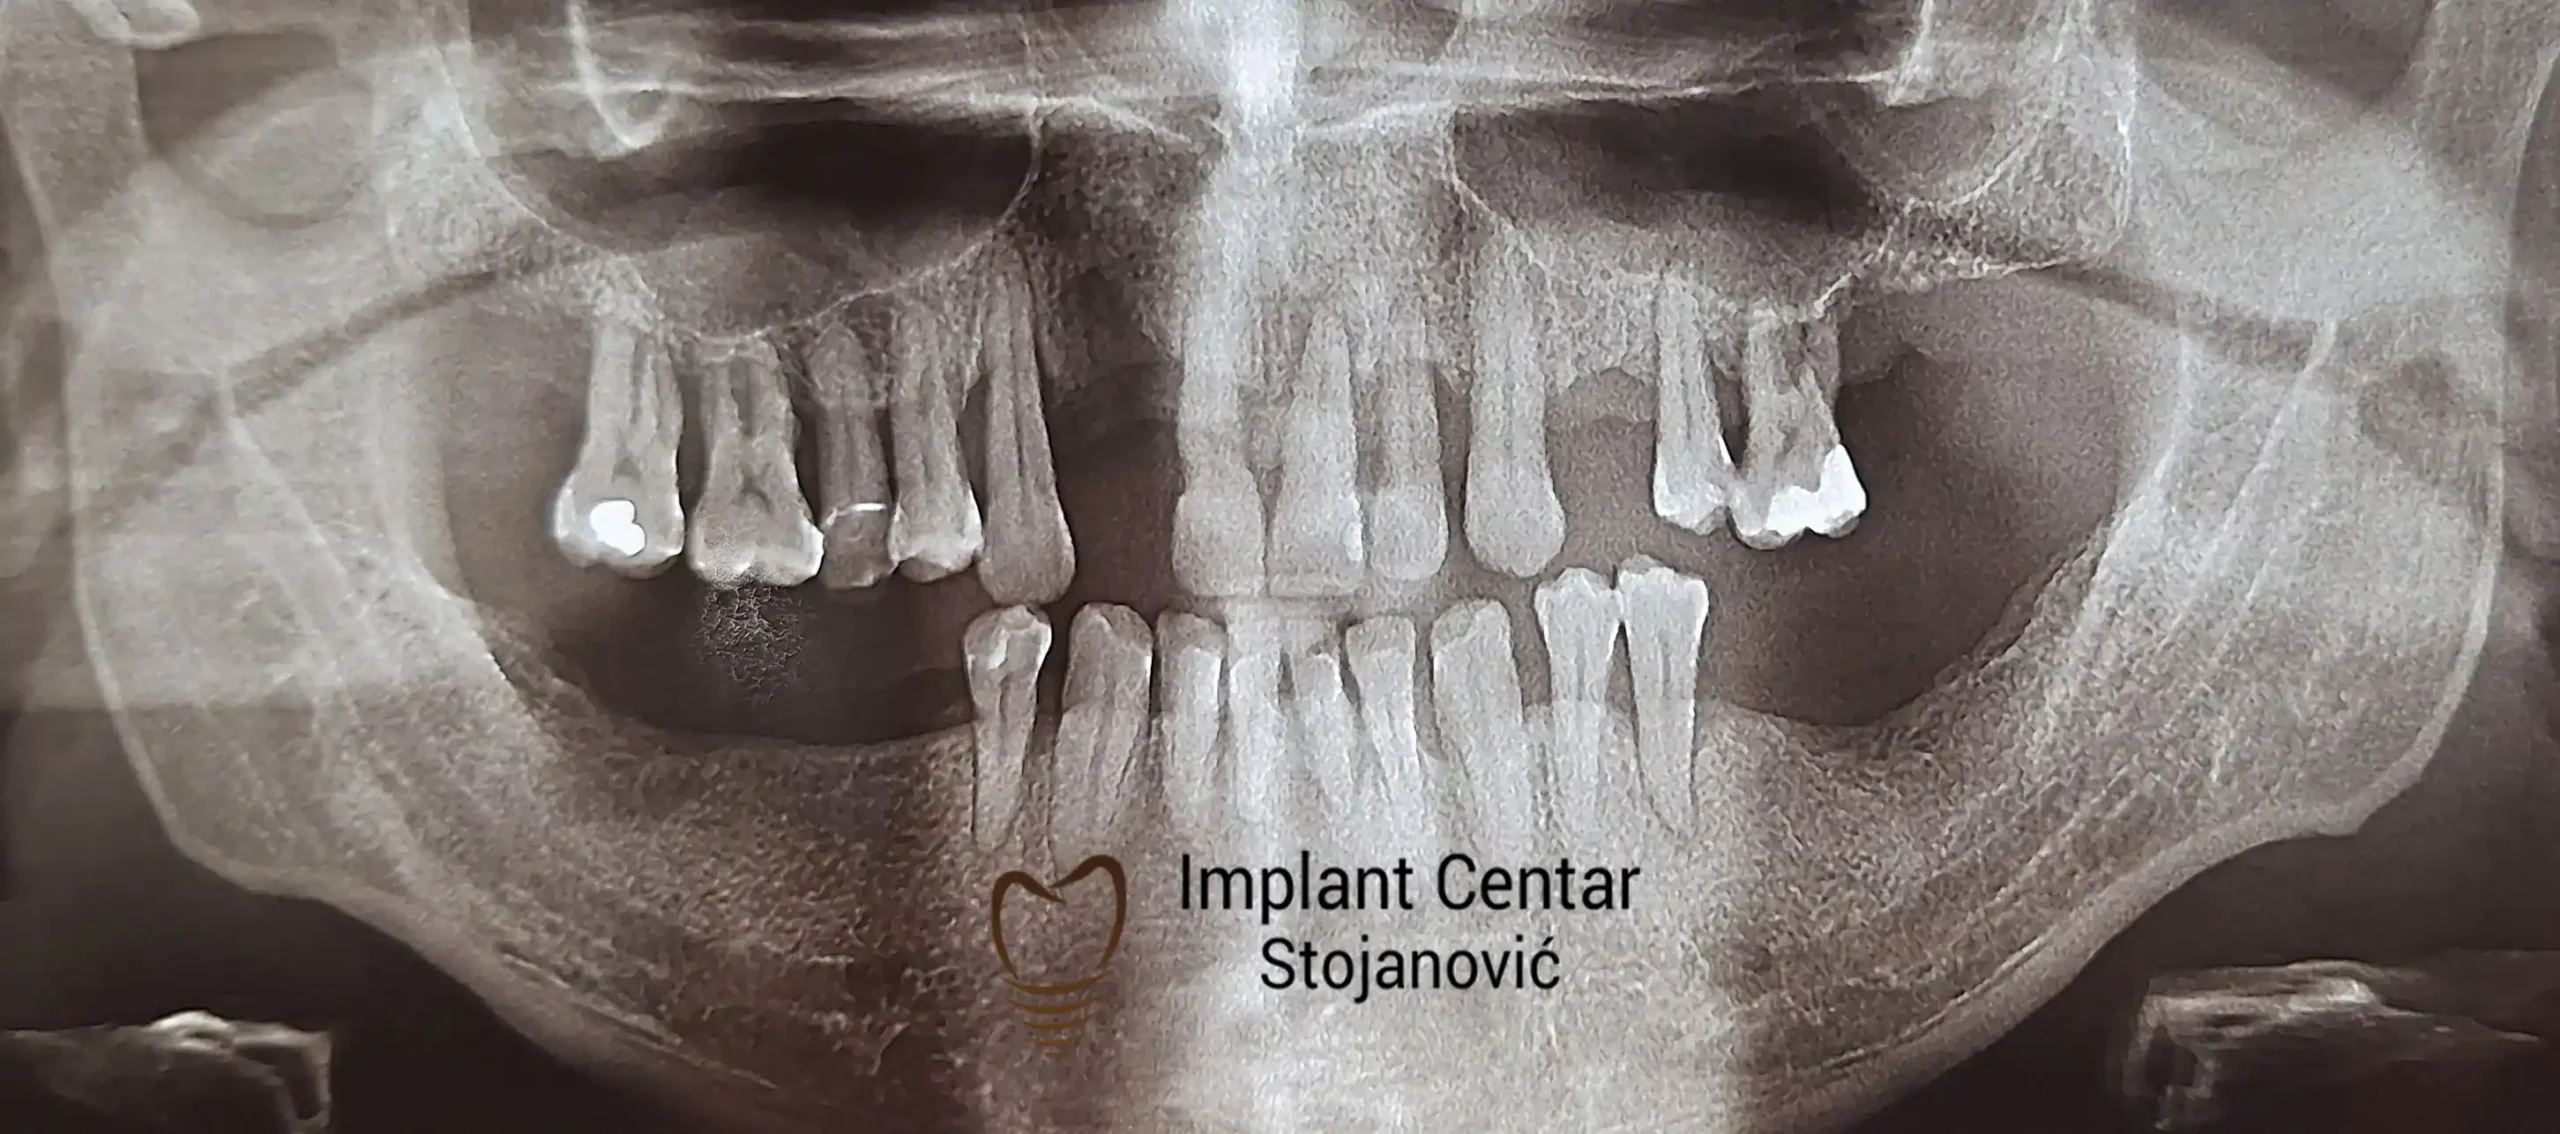

Na slici 1. i slici 2. prikazan je izgled pacijenta pre početka terapije – klinički i rendgenološki.

Nakon vađenja zuba, ugrađeni su implantati. Na slici 3 prikazan je ortopan snimak sa ugrđenim implantatima. Tokom perioda osteointegracije, pacijent je bio zbrinut fiksnim privremenim krunicama na implantatima, koje su izrađene samo dva dana nakon hirurške intervencije.